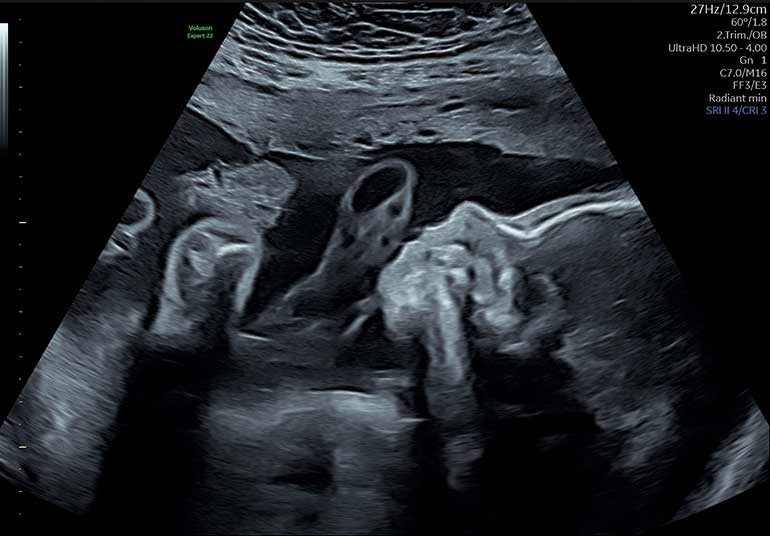

Dr. Frenzel: Das Ersttrimester-Screening und die frühe Feindiagnostik sind für jede Schwangere sinnvoll – egal welchen Alters. Beim Ersttrimester-Screening, das zwischen der 11. und 14. Schwangerschaftswoche durchgeführt wird, wird der Ultraschall genutzt, um verschiedene Aspekte der Entwicklung des Babys zu überprüfen. Dazu gehören die Messung der Nackenfalte, die Untersuchung des Herzens, der Organe, der Gliedmaßen sowie der Gefäße der Mutter und des Babys. Zusätzlich werden körperliche Marker des Babys gemessen, die Hinweise auf genetische Störungen oder mögliche Herzfehler geben können. Am Ende des Ersttrimester-Screenings erhält die Schwangere zusätzlich eine Einschätzung ihres individuellen Risikos, ob sie im weiteren Verlauf eine Präeklampsie entwickeln könnte, ob die Plazenta in der Schwangerschaft ausreichend funktioniert sowie eine Aussage zum Risiko einer Frühgeburt.

Prof. Dr. Offermann: Das Ersttrimester-Screening liefert erste Hinweise auf mögliche Risiken, wie genetische Störungen oder Auffälligkeiten in der frühen Entwicklung des Babys. Es kann jedoch nicht alle Fehlbildungen oder Entwicklungsstörungen erkennen. Die Feindiagnostik, die die in der Regel zwischen der 20. und 22. Schwangerschaftswoche durchgeführt wird, bietet eine viel detailliertere Untersuchung. Sie ermöglicht eine genauere Beurteilung der Organe und Strukturen des Babys, die erst im zweiten Schwangerschaftstrimester vollständig entwickelt sind. Dadurch können Fehlbildungen, die im ersten Trimester noch nicht sichtbar waren, frühzeitig erkannt und besser bewertet werden. Beide Untersuchungen ergänzen sich also, um eine möglichst vollständige Einschätzung der Gesundheit des Babys zu geben.